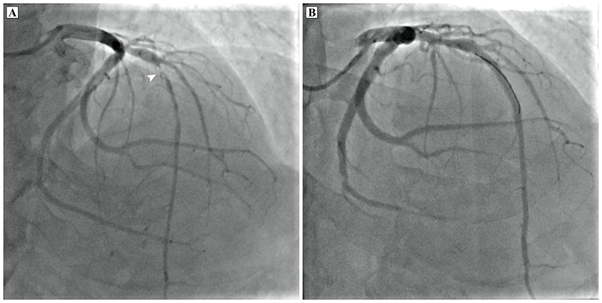

A 64-year-old man with no prior cardiac illness presented with typical angina with ST-T wave changes on electrocardiograph (ECG) and elevated cardiac troponins requiring emergent catheter angiogram which showed 95% stenosis in the mid left anterior descending artery (LAD) for which percutaneous coronary intervention was done (Figure 1). The ECG and 2D-transthoracic echocardiogram (TTE) also showed changes of asymmetric left ventricular hypertrophy with a significant outflow tract gradient consistent with obstructive HCM. As a part of the workup for HCM, the patient underwent a CMR imaging that revealed asymmetric thickened basal and mid septum (22 mm in end diastole), with relatively thinned out and hypokinetic left ventricular (LV) apex. There was subendocardial LGE along the LAD territory with midmyocardial enhancement involving the hypertrophied septum (Figure 2).

Figure 2 Cardiac MRI (a) steady state free precision diastolic short axis image demonstrating asymmetric septal predominant hypertrophic cardiomyopathy (thick arrows). (b) Horizontal long axis and (c) short axis late gadolinium enhancement images show subendocardial late gadolinium enhancement (thin arrows) with thinning of apex which showed hypokinesis on cine imaging and midmyocardial patchy fibrosis in thickened septum (thick arrows).